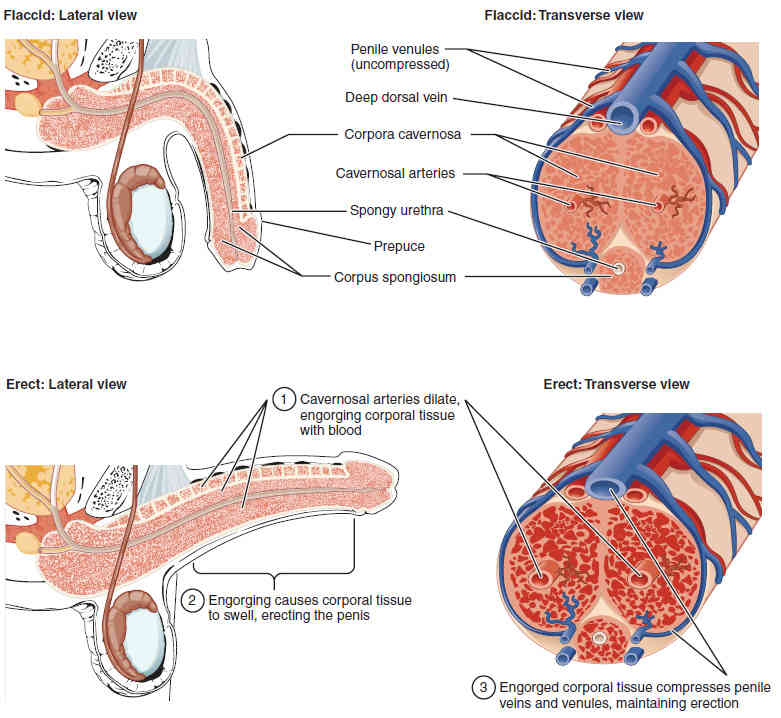

This page is under construction. For now, it is just a resource of the images found in the OpenStax Anatomy and Physiology Handbook. It wil slowly change into a revision tool. Each slide has a number. Use this to refer to the slide. When completed, it will have an unlabelled section, with labelled slides in parallel. On the unlabelled slides, write your answer and use the labelled slide to assess yourself. Keep track by also noting the number on each slide. Improvement at each attempt is important, more so than full marks on a first attempt.